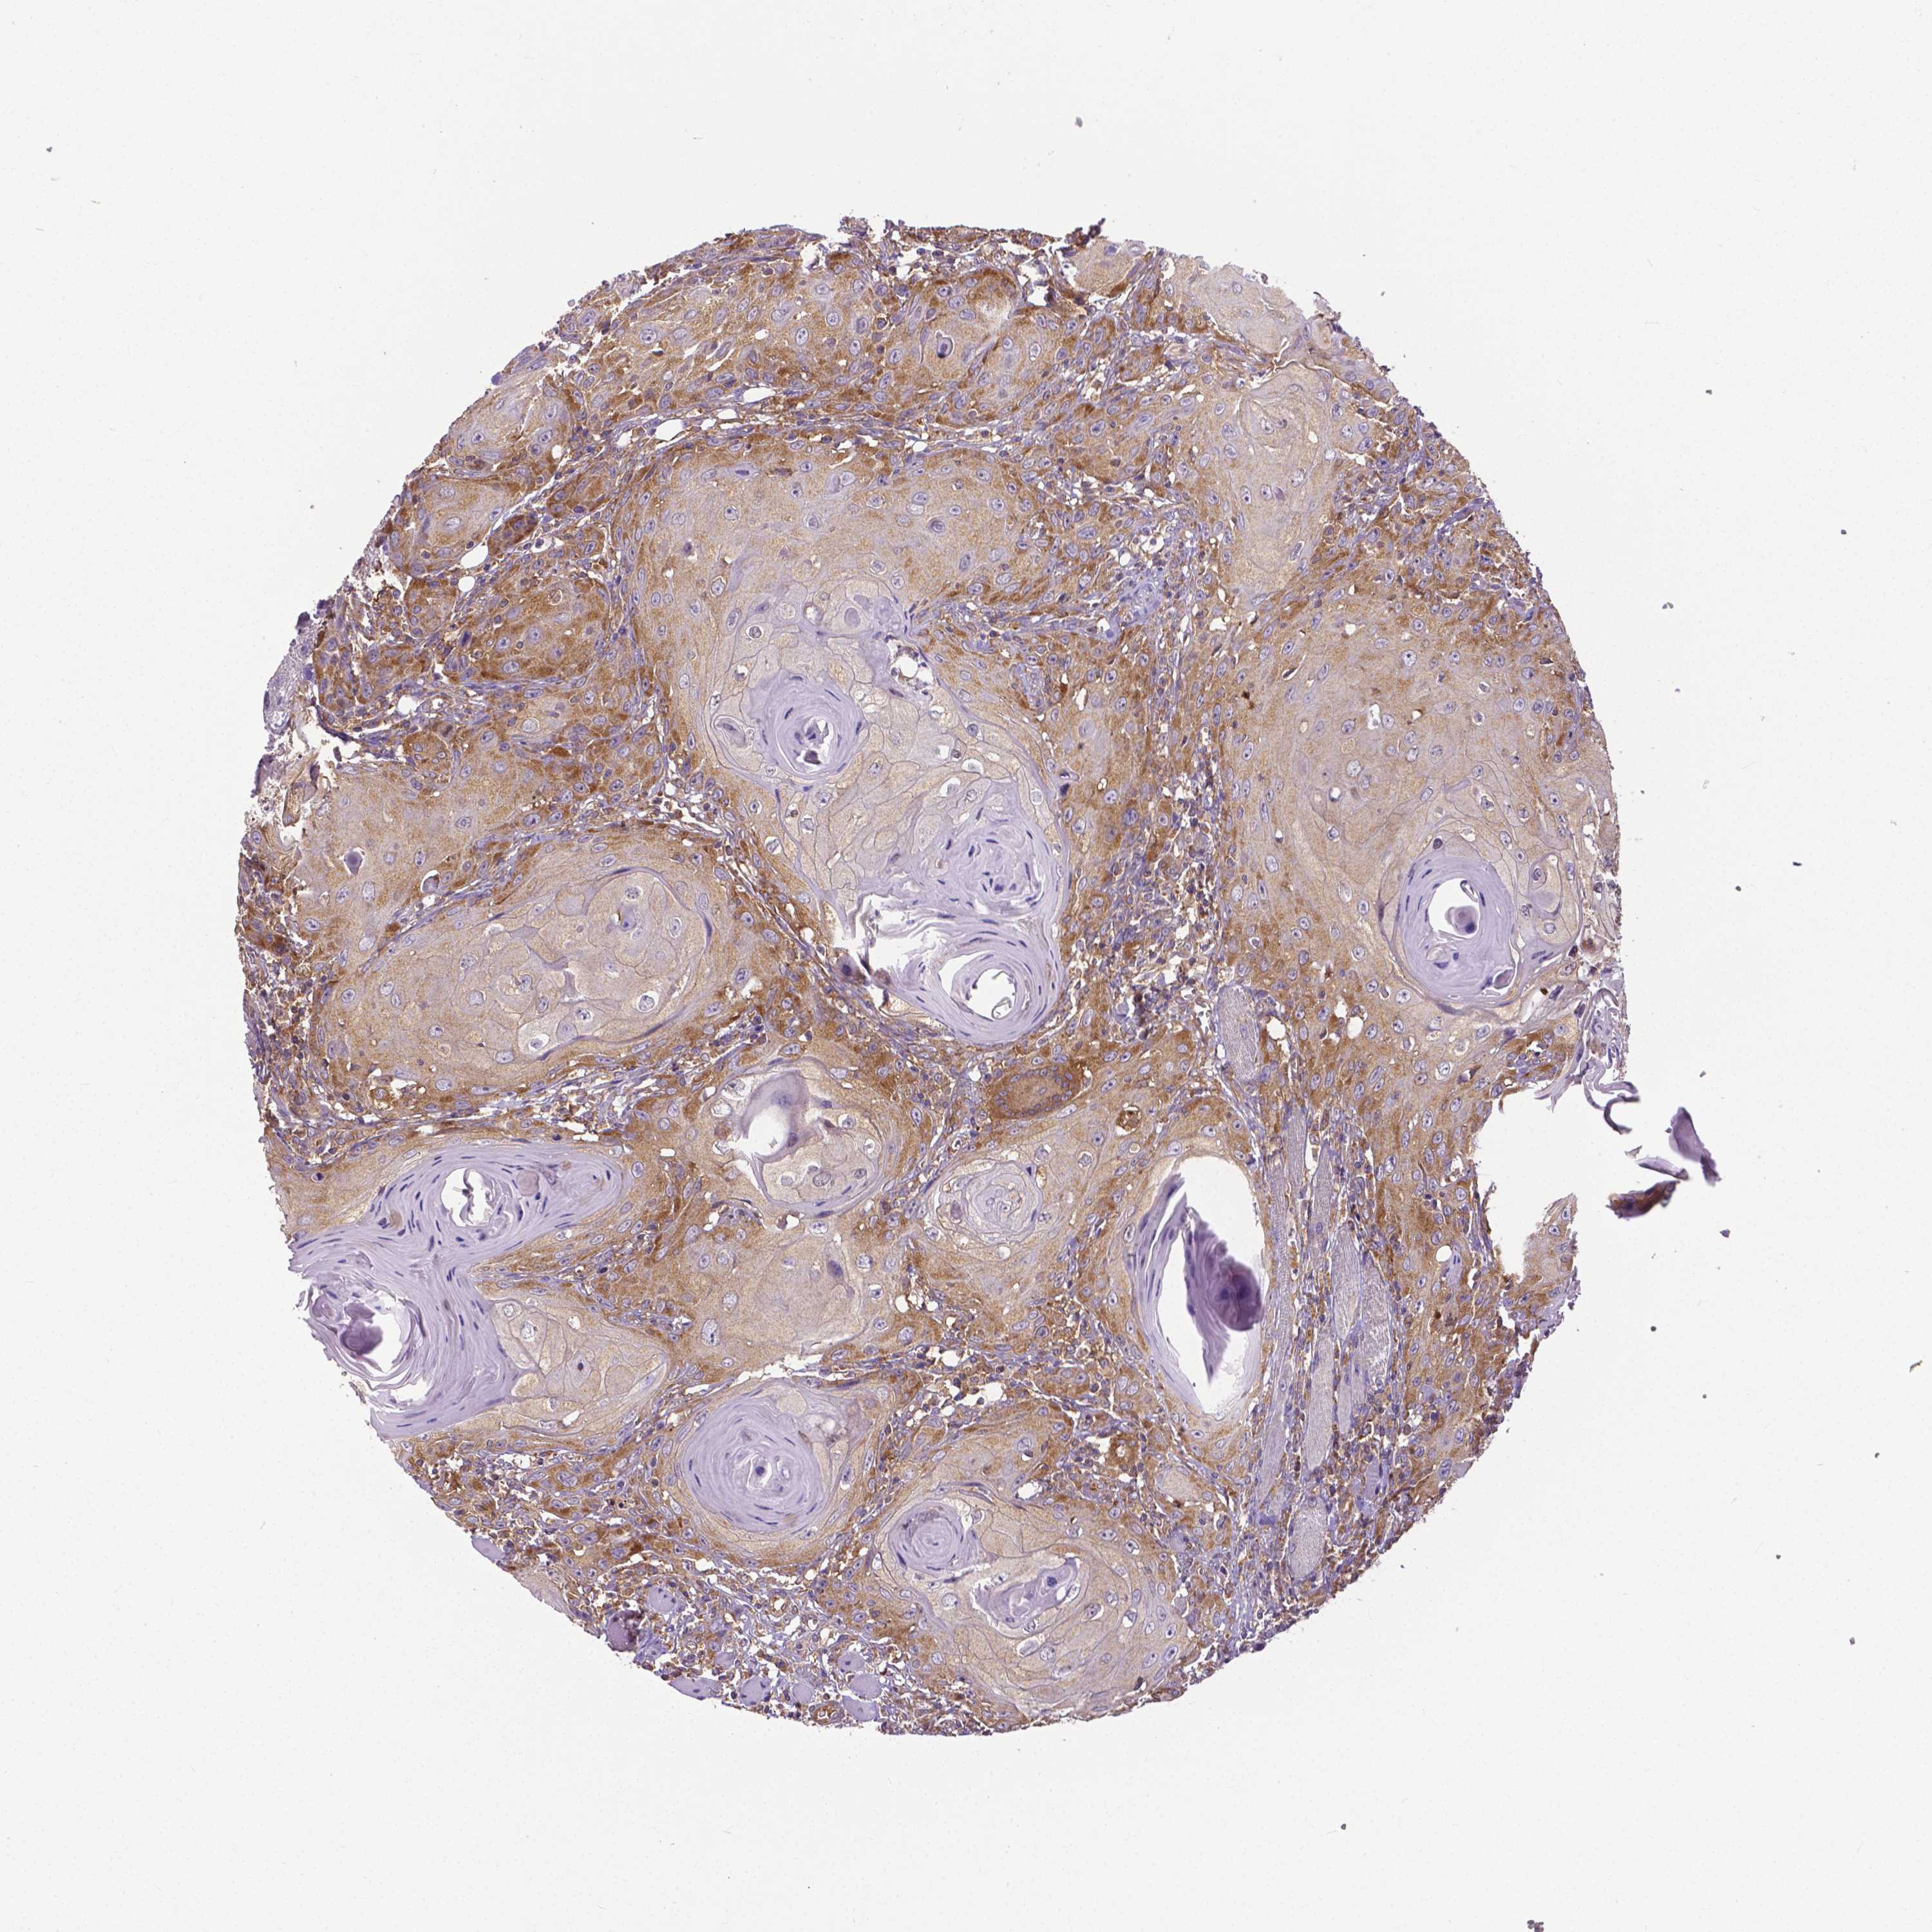

HEAD AND NECK CANCER - Protein expressioni

A mouse-over function shows sample information and annotation data. Click on an image to view it in a full screen mode. Samples can be filtered based on level of antibody staining by selecting one or several of the following categories: high, medium, low and not detected. The assay and annotation is described here.

Antibody stainingi

Antibody staining in the annotated cell types in the current human tissue is reported as not detected, low, medium, or high, based on conventional immunohistochemistry profiling in selected tissues. This score is based on the combination of the staining intensity and fraction of stained cells.

Each image is clickable and will lead to virtual microscopy that enables deeper exploration of all samples and also displays staining intensity scores, fraction scores and subcellular localization as well as patient and tissue information for each sample.

Antibody HPA000694

Antibody CAB068185

Staining

High

Medium

Low

Not detected

Intensity

Strong

Moderate

Weak

Negative

Quantity

>75%

75%-25%

<25%

None

Location

Nuclear

Cytoplasmic/membranous

Cytoplasmic/membranous,nuclear

Squamous cell carcinoma, NOS